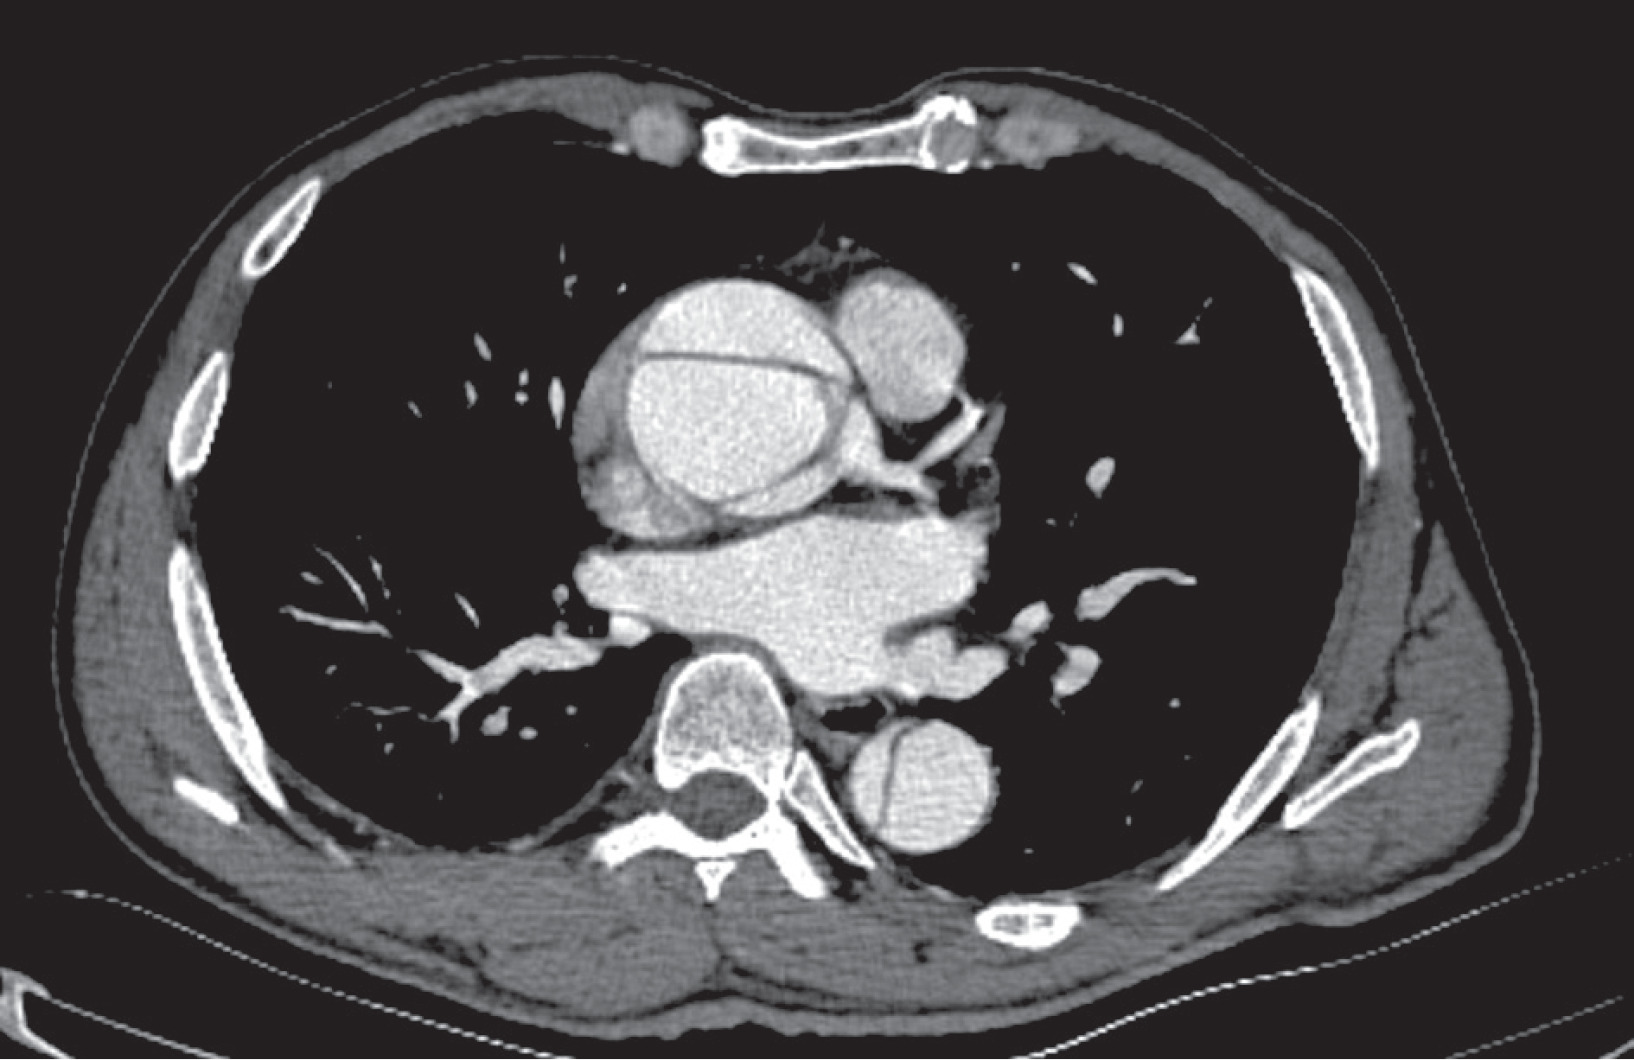

Figure 1

A – Preoperative computed tomography angiography(CTA) image showing innominate artery dissection (blue arrow) and left carotid artery occlusion with thrombi (yellow arrow). B – Postoperative CTA image of the same patient showing the innominate artery cannulation site (arrow)

The patients’ baseline demographic characteristics are summarized in Table I. Forty-six patients who underwent emergency surgical repair for ATAAD between January 2021 and April 2024 were retrospectively evaluated. ATAAD was defined as an aortic dissection (AD) detected within 14 days after the onset of symptoms. The anatomy of AD was classified according to the DeBakey classification [8]. Prior to the procedures, all patients underwent transthoracic echocardiography (TTE) performed by expert cardiologists. The radiologist and cardiovascular surgery team then performed computed tomography angiography (CTA), thoroughly examined the images, and verified the findings intraoperatively (Figures 1, 2). At presentation, dissection extent was DeBakey type I in 37 (80.4%) and type II in 9 (19.6%). The patients were grouped as those with right AXA cannulation (group 1, n = 18) and IA cannulation (group 2, n = 28). The groups were compared based on preoperative, intraoperative, and postoperative data. The GERAADA score was calculated individually for each patient using a web-based tool by a cardiovascular surgeon who was blind to the study [9]. All procedures were carried out by different surgeons using similar techniques.